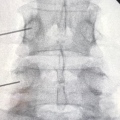

Fotos